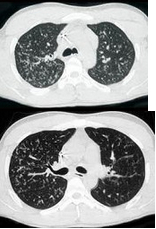

男,26岁,发热,夜间盗汗,咳嗽半月余,结合CT检查,最可能的诊断是( )

A:粟粒型肺结核

B:间质性肺炎

C:弥漫型肺癌

D:肺转移瘤

E:矽肺